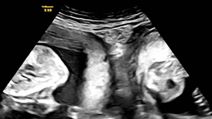

Trudnoća

Trudni ste i nosite blizance? Ovo su osnovne razlike između jednojajčanih i dvojajčanih blizanaca

Mogu li već nakon test znati nosim li blizance? Stručnjaci nabrojali 6 simptoma koji ukazuju na višeplodnu trudnoću